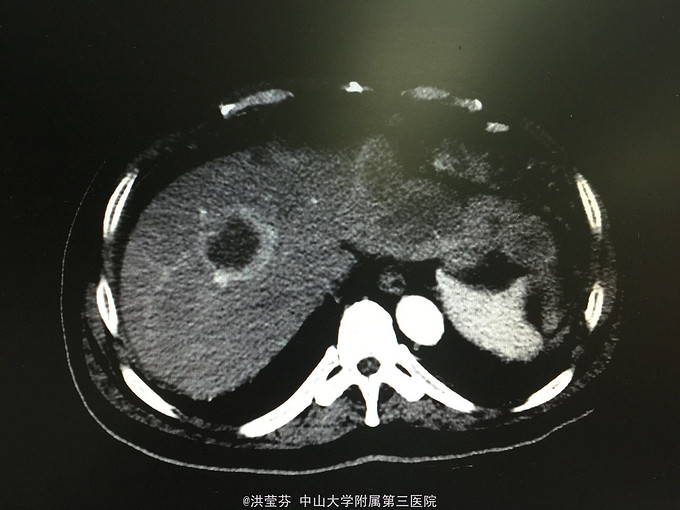

查体:上腹部轻压痛,无反跳痛。 辅助检查:上腹部CT增强提示:肝S2/3/4段恶性肿瘤,肝内多发子灶,肝左静脉及门静脉左、右支受侵;腹腔多发转移瘤;肝门部、腹膜后多发肿大淋巴结;门静脉海绵样变;少量腹水。胸部CT提示:1、双肺多发小结节,结合病史,考虑转移瘤;纵膈、双侧肺门多发肿大淋巴结。2.双肺炎症;左侧胸腔少量积液。CA125 555.1IU/nl,CA199 1093.5IU/nl。

诊断考虑胆管细胞癌可能性大,予完善肝穿刺,活检病理示:符合中分化腺癌,胆管细胞癌可能性大。免疫组化结果示:Hep(-),CK(+),CK19(+),CEA(-),CDX-2(-),DK20(-),Ki 67(约15%),TTF-1(-)。诊断明确肝内胆管细胞癌,IV期,无明显化疗禁忌,予GP方案化疗,辅以护胃、护肝、止吐等治疗。

2程化疗后复查CT评价疗效疾病进展,并腹水明显增多,予加强支持治疗后予改行减量FOLFOX方案化疗,过程顺利。患者精神较差,症状上改善不明显,预后差。 这种情况大家还有什么治疗方案可以推荐的吗?